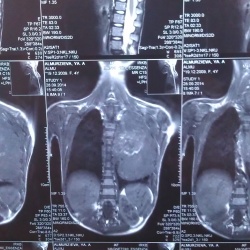

05.10.2015 - 17:59

Новорожденный, Аспирационная пневмония. На одном из снимков с выраженным разворотом хорошо видны шаровидные тени. Что это?